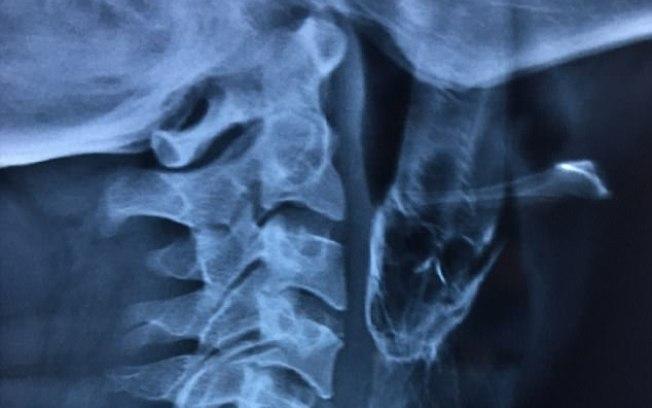

Encaminhado para um hospital universitário, ele tirou um Raio X para que os profissionais pudessem dimensiosar o tamanho do que eles estavam lidando, mas a odisseia do pescador estava longe de terminar por aí.